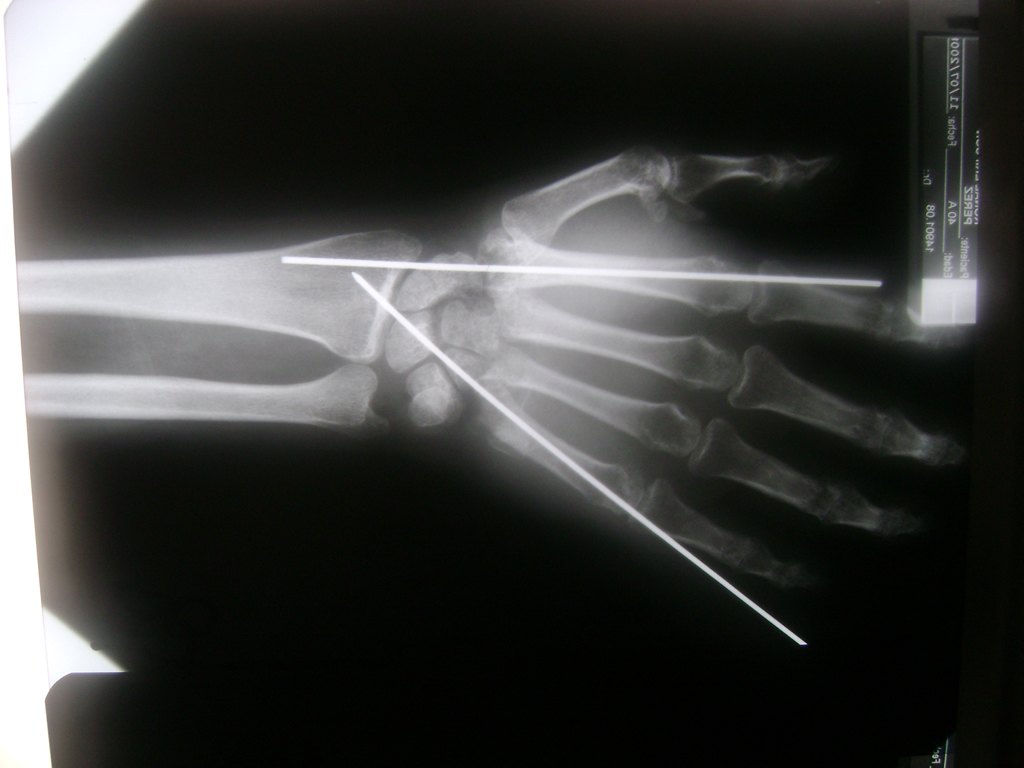

Los procedimientos más comunes en cirugía de la mano son aquellos destinados a reparar traumatismos, incluyendo lesiones de tendones, nervios, vasos sanguíneos, y articulaciones; huesos fracturados; y quemaduras, cortes, y otros daños de la piel.